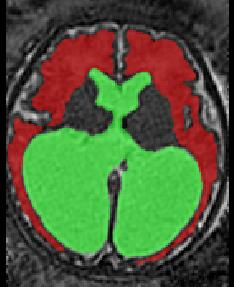

Limiting failures of machine learning systems is of paramount importance for safety-critical applications. In order to improve the robustness of machine learning systems, Distributionally Robust Optimization (DRO) has been proposed as a generalization of Empirical Risk Minimization (ERM). However, its use in deep learning has been severely restricted due to the relative inefficiency of the optimizers available for DRO in comparison to the wide-spread variants of Stochastic Gradient Descent (SGD) optimizers for ERM. We propose SGD with hardness weighted sampling, a principled and efficient optimization method for DRO in machine learning that is particularly suited in the context of deep learning. Similar to a hard example mining strategy in practice, the proposed algorithm is straightforward to implement and computationally as efficient as SGD-based optimizers used for deep learning, requiring minimal overhead computation. In contrast to typical ad hoc hard mining approaches, we prove the convergence of our DRO algorithm for over-parameterized deep learning networks with ReLU activation and a finite number of layers and parameters. Our experiments on fetal brain 3D MRI segmentation and brain tumor segmentation in MRI demonstrate the feasibility and the usefulness of our approach. Using our hardness weighted sampling for training a state-of-the-art deep learning pipeline leads to improved robustness to anatomical variabilities in automatic fetal brain 3D MRI segmentation using deep learning and to improved robustness to the image protocol variations in brain tumor segmentation. Our code is available at https://github.com/LucasFidon/HardnessWeightedSampler.